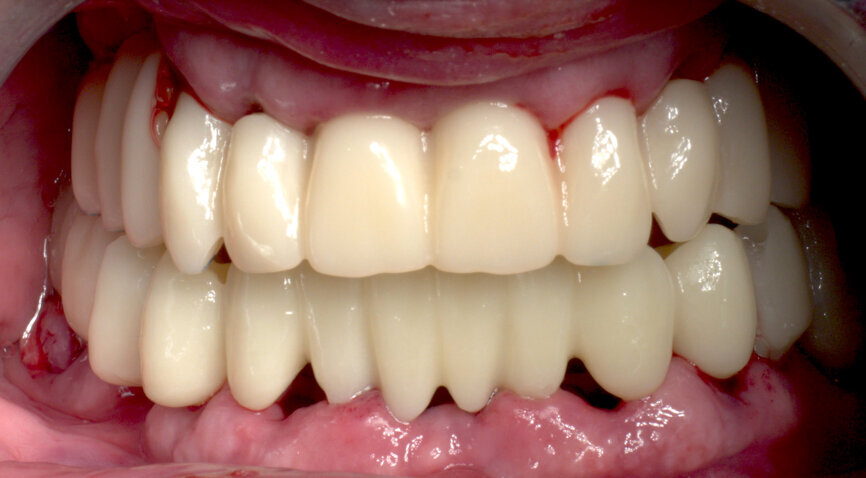

Returning to the patient, the healing caps were removed (Fig. 19), and the prosthesis was placed, allowing for a passive fit on the abutments, with an initial handpiece tightening of each SRA screw to 5 N cm. After the seating was checked, the torque of each SRA screw was increased, also with the handpiece, to 35 N cm (Fig. 20). The occlusion was checked and contacts were inspected (Fig. 21). The screw holes were sealed with PTFE and a temporary filling material. A panoramic X-ray was taken, and SRA screw positions were evaluated to confirm the perfect temporary bridge fit (Fig. 22). The patient was discharged on 500 mg of amoxicillin every 8 hours and 25 mg of dexketoprofen every 12 hours for one week. Oral hygiene and diet instructions were given, and a one-week follow-up appointment was scheduled.

Bearing in mind that this is a one-day treatment, the overall treatment time per jaw is about 3–4 hours from the beginning to the end of the procedure. With this minimally invasive protocol, postoperative pain, swelling and discomfort are minimal. Patients are able to recover their health and social life immediately, without the psychological and social impairment associated with longer classical procedures.